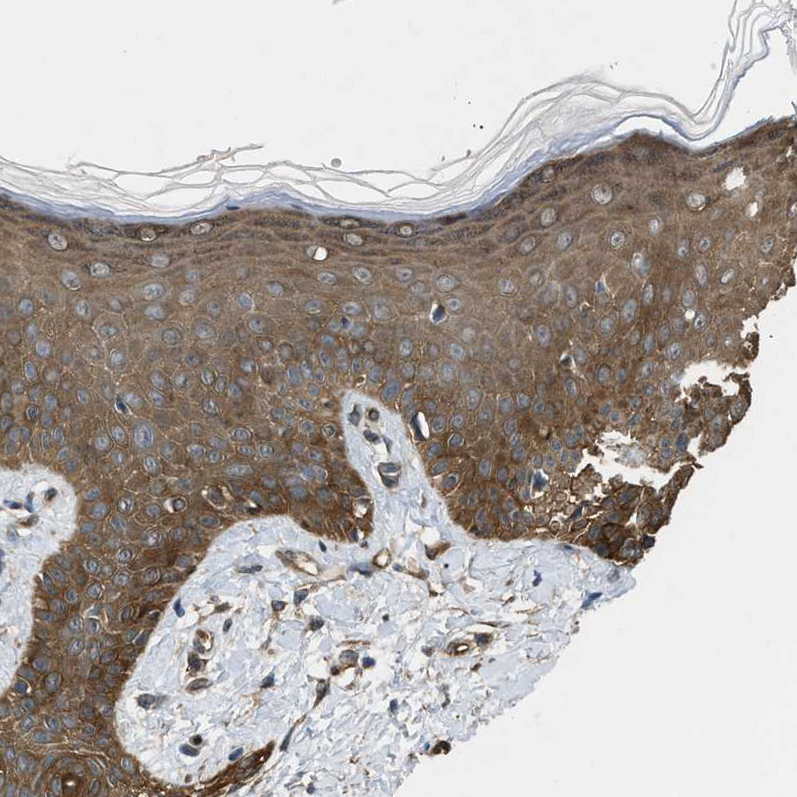

Immunohistochemical staining of human cerebellum, prostate, skeletal muscle and skin using Anti-BAG3 antibody HPA020586 (A) shows similar protein distribution across tissues to independent antibody HPA018493 (B).